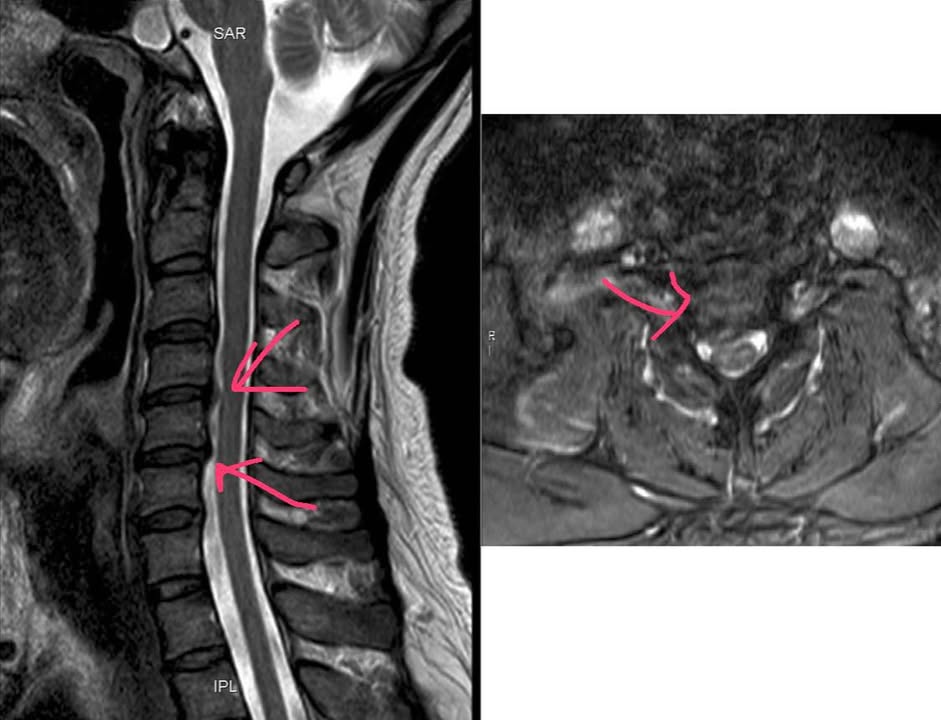

診斷:C4/C5 ;C5/C6椎間盤突出壓迫脊髓神經根